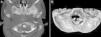

Caso clínicoPresentamos un caso excepcional de mielopatía por compresión a nivel del atlas en un niño de 5 años con síndrome de Down provocado por una anomalía del desarrollo del arco posterior de C1. Se realizó una laminectomía posterior a ese nivel con mejoría de la sintomatología previa.

Case reportWe report an exceptional case of myelopathy due to compression at the level of the atlas in a 5-year-old boy with Down syndrome provoked by a developmental anomaly of the posterior arch of C1. A posterior laminectomy was achieved at that level with improvement of the previous symptoms.